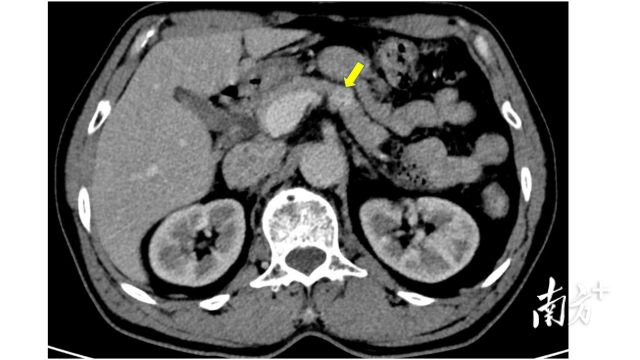

通过与影像科反复讨论,医生为吴先生制定详细的影像扫描参数,终于从胰腺动脉灌注CT平扫成像、腹部MR平扫+增强血管成像找到突破口,发现胰腺体部大小约10mm的占位性病变,疑似胰岛素瘤,垂体MR未见明显异常。